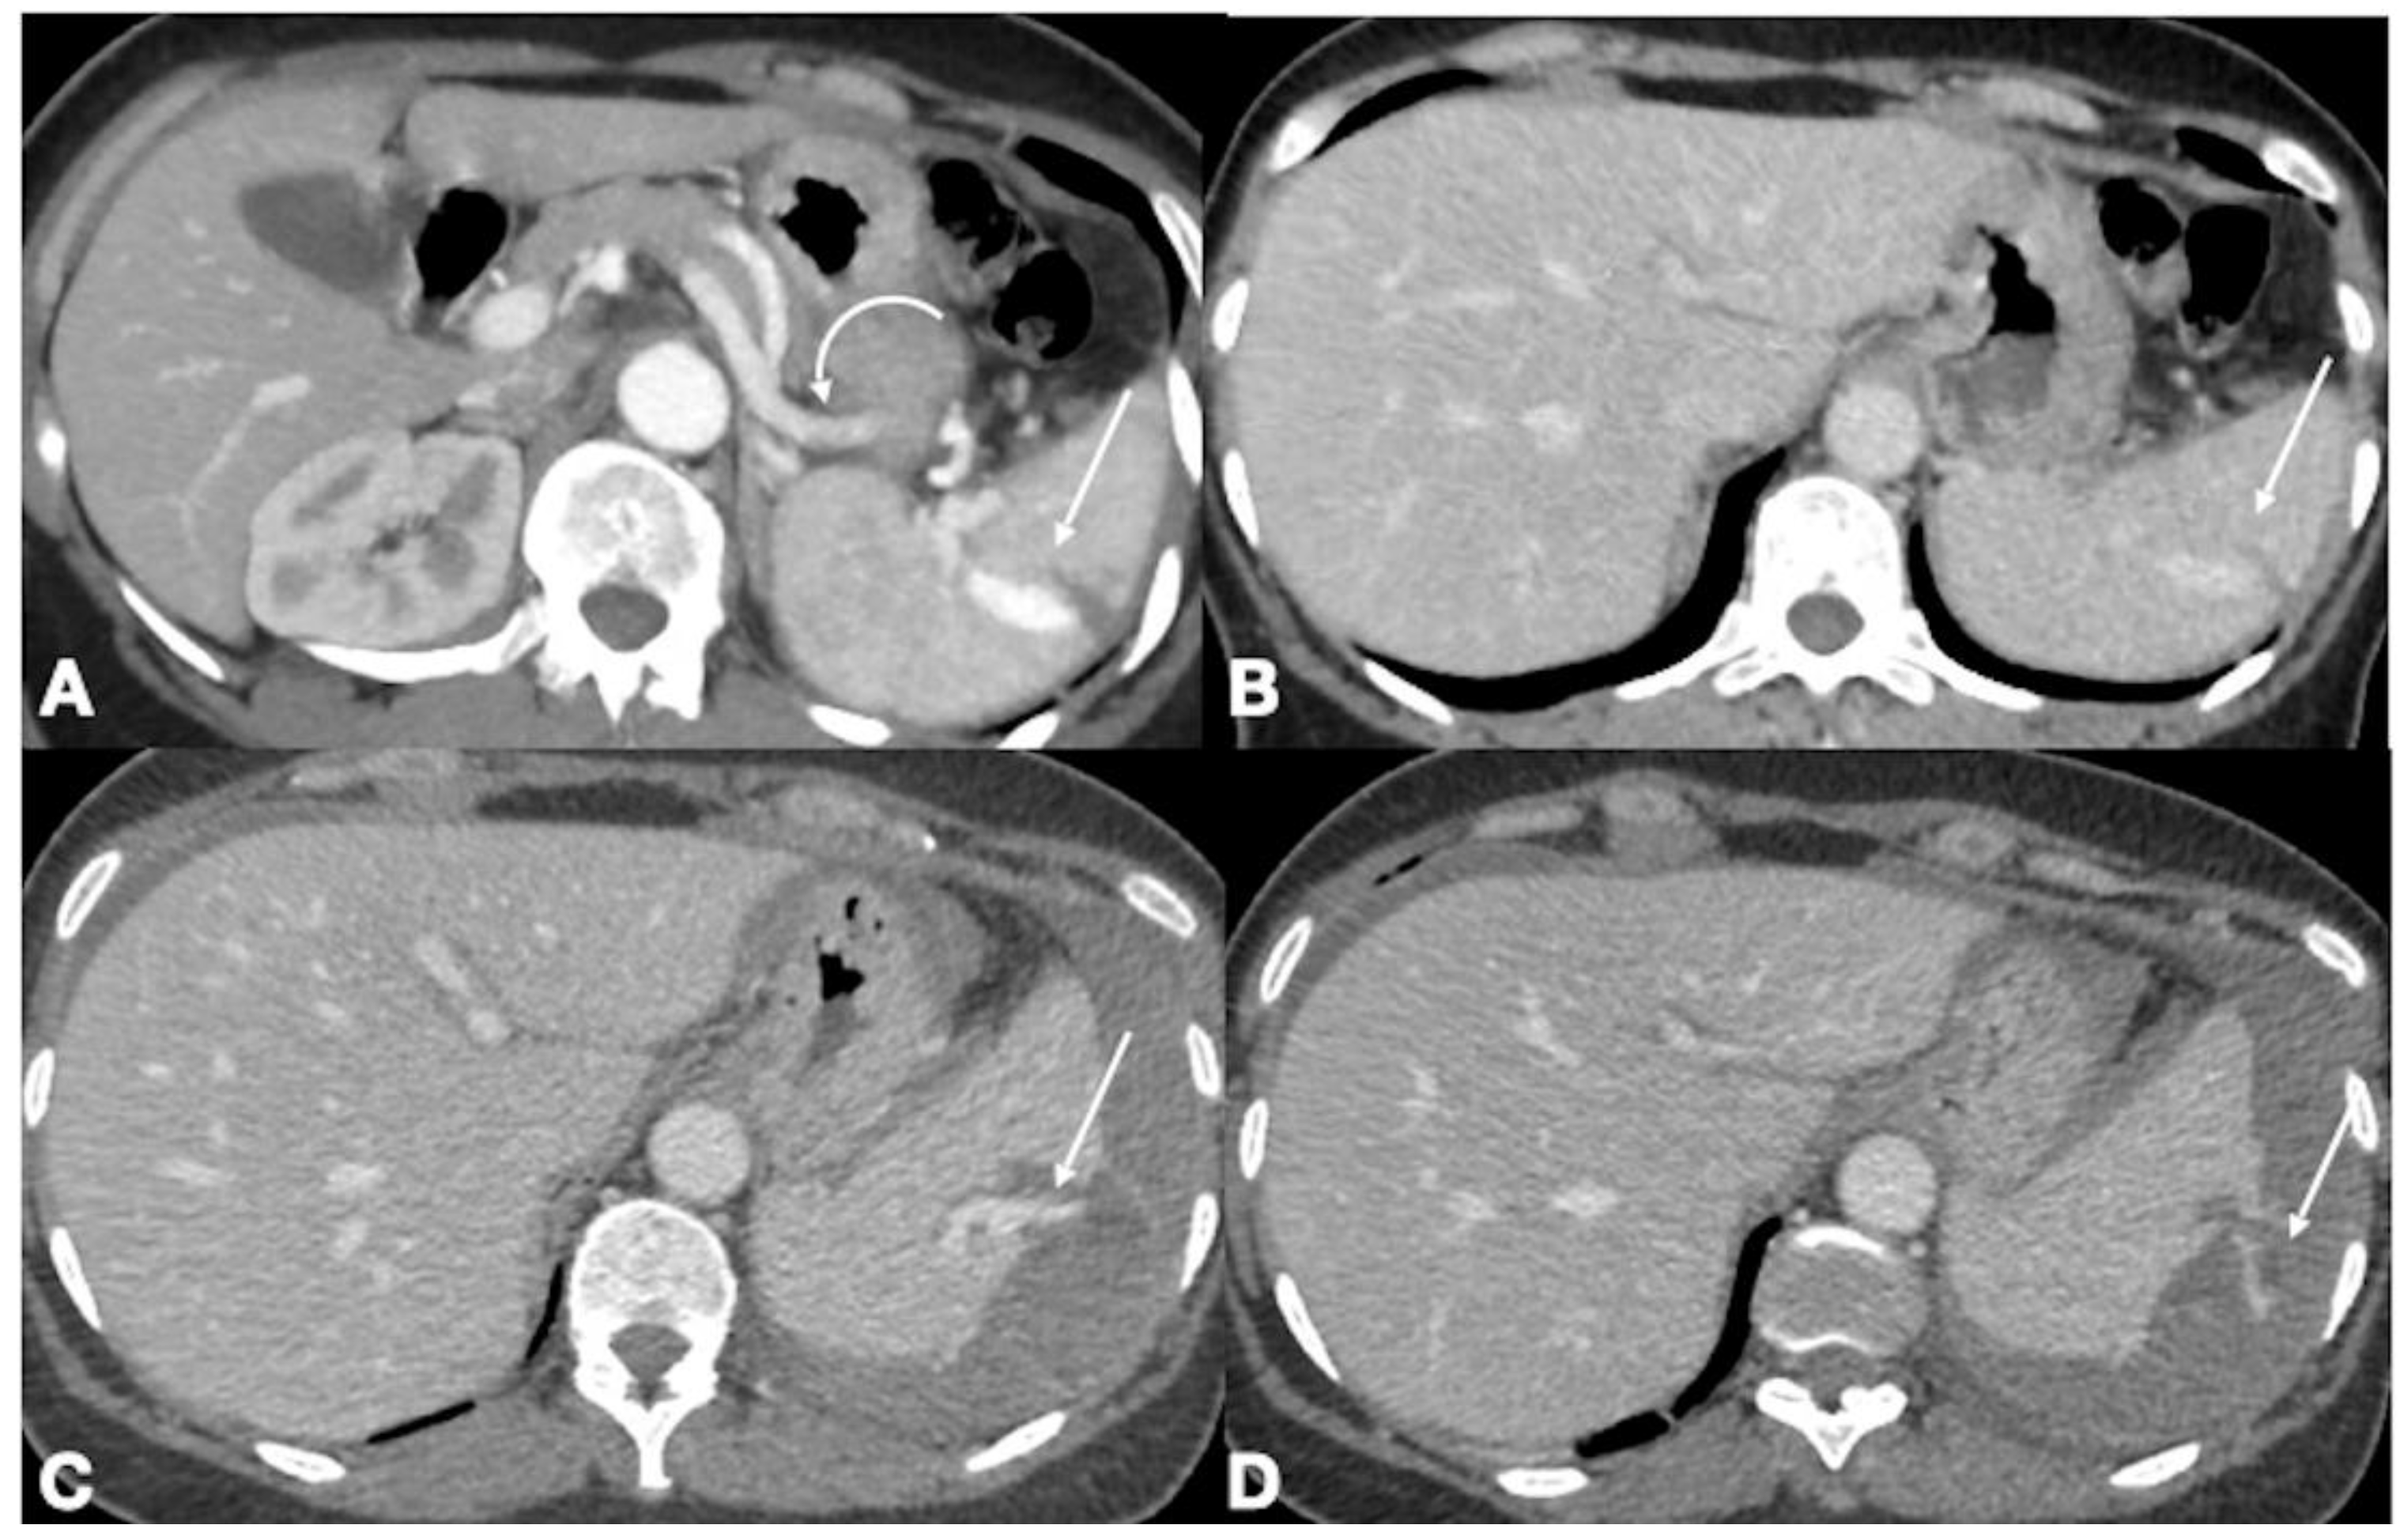

- Iacobellis, F.; Scaglione, M.; Brillantino, A.; Scuderi, M.G.; Giurazza, F.; Grassi, R.; Noschese, G.; Niola, R.; Al Zuhir, N.Y.S.; Romano, L. The additional value of the arterial phase in the CT assessment of liver vascular injuries after high-energy blunt trauma. Emerg. Radiol. 2019, 26, 647–654. [Google Scholar] [CrossRef]

- Iacobellis, F.; Ierardi, A.M.; Mazzei, M.A.; Biasina, A.M.; Carrafiello, G.; Nicola, R.; Scaglione, M. Dual-phase CT for the assessment of acute vascular injuries in high-energy blunt trauma: The imaging findings and management implications. Br. J. Radiol. 2016, 89, 20150952. [Google Scholar] [CrossRef]